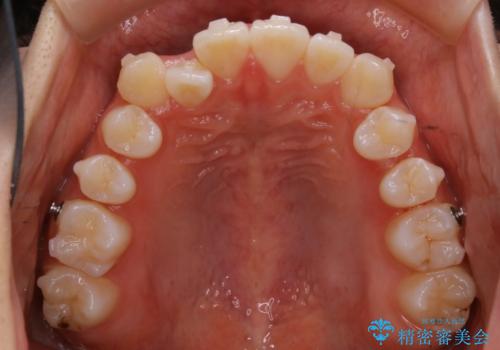

こちらの患者様の場合、上の前歯のガタつきが原因で口を閉じる際に上下の前歯の先端同士が先に当たってしまい、そこからさらに深く噛み込もうとすると下顎が前にずれていってしまうという、機能性の反対咬合であることが検査の結果わかりました。

そのため、まずは上顎の前歯のガタつきを改善していき、前歯が先に当たってしまうという症状を改善し噛み込む位置を後方の本来の位置に誘導する方法をとりました。